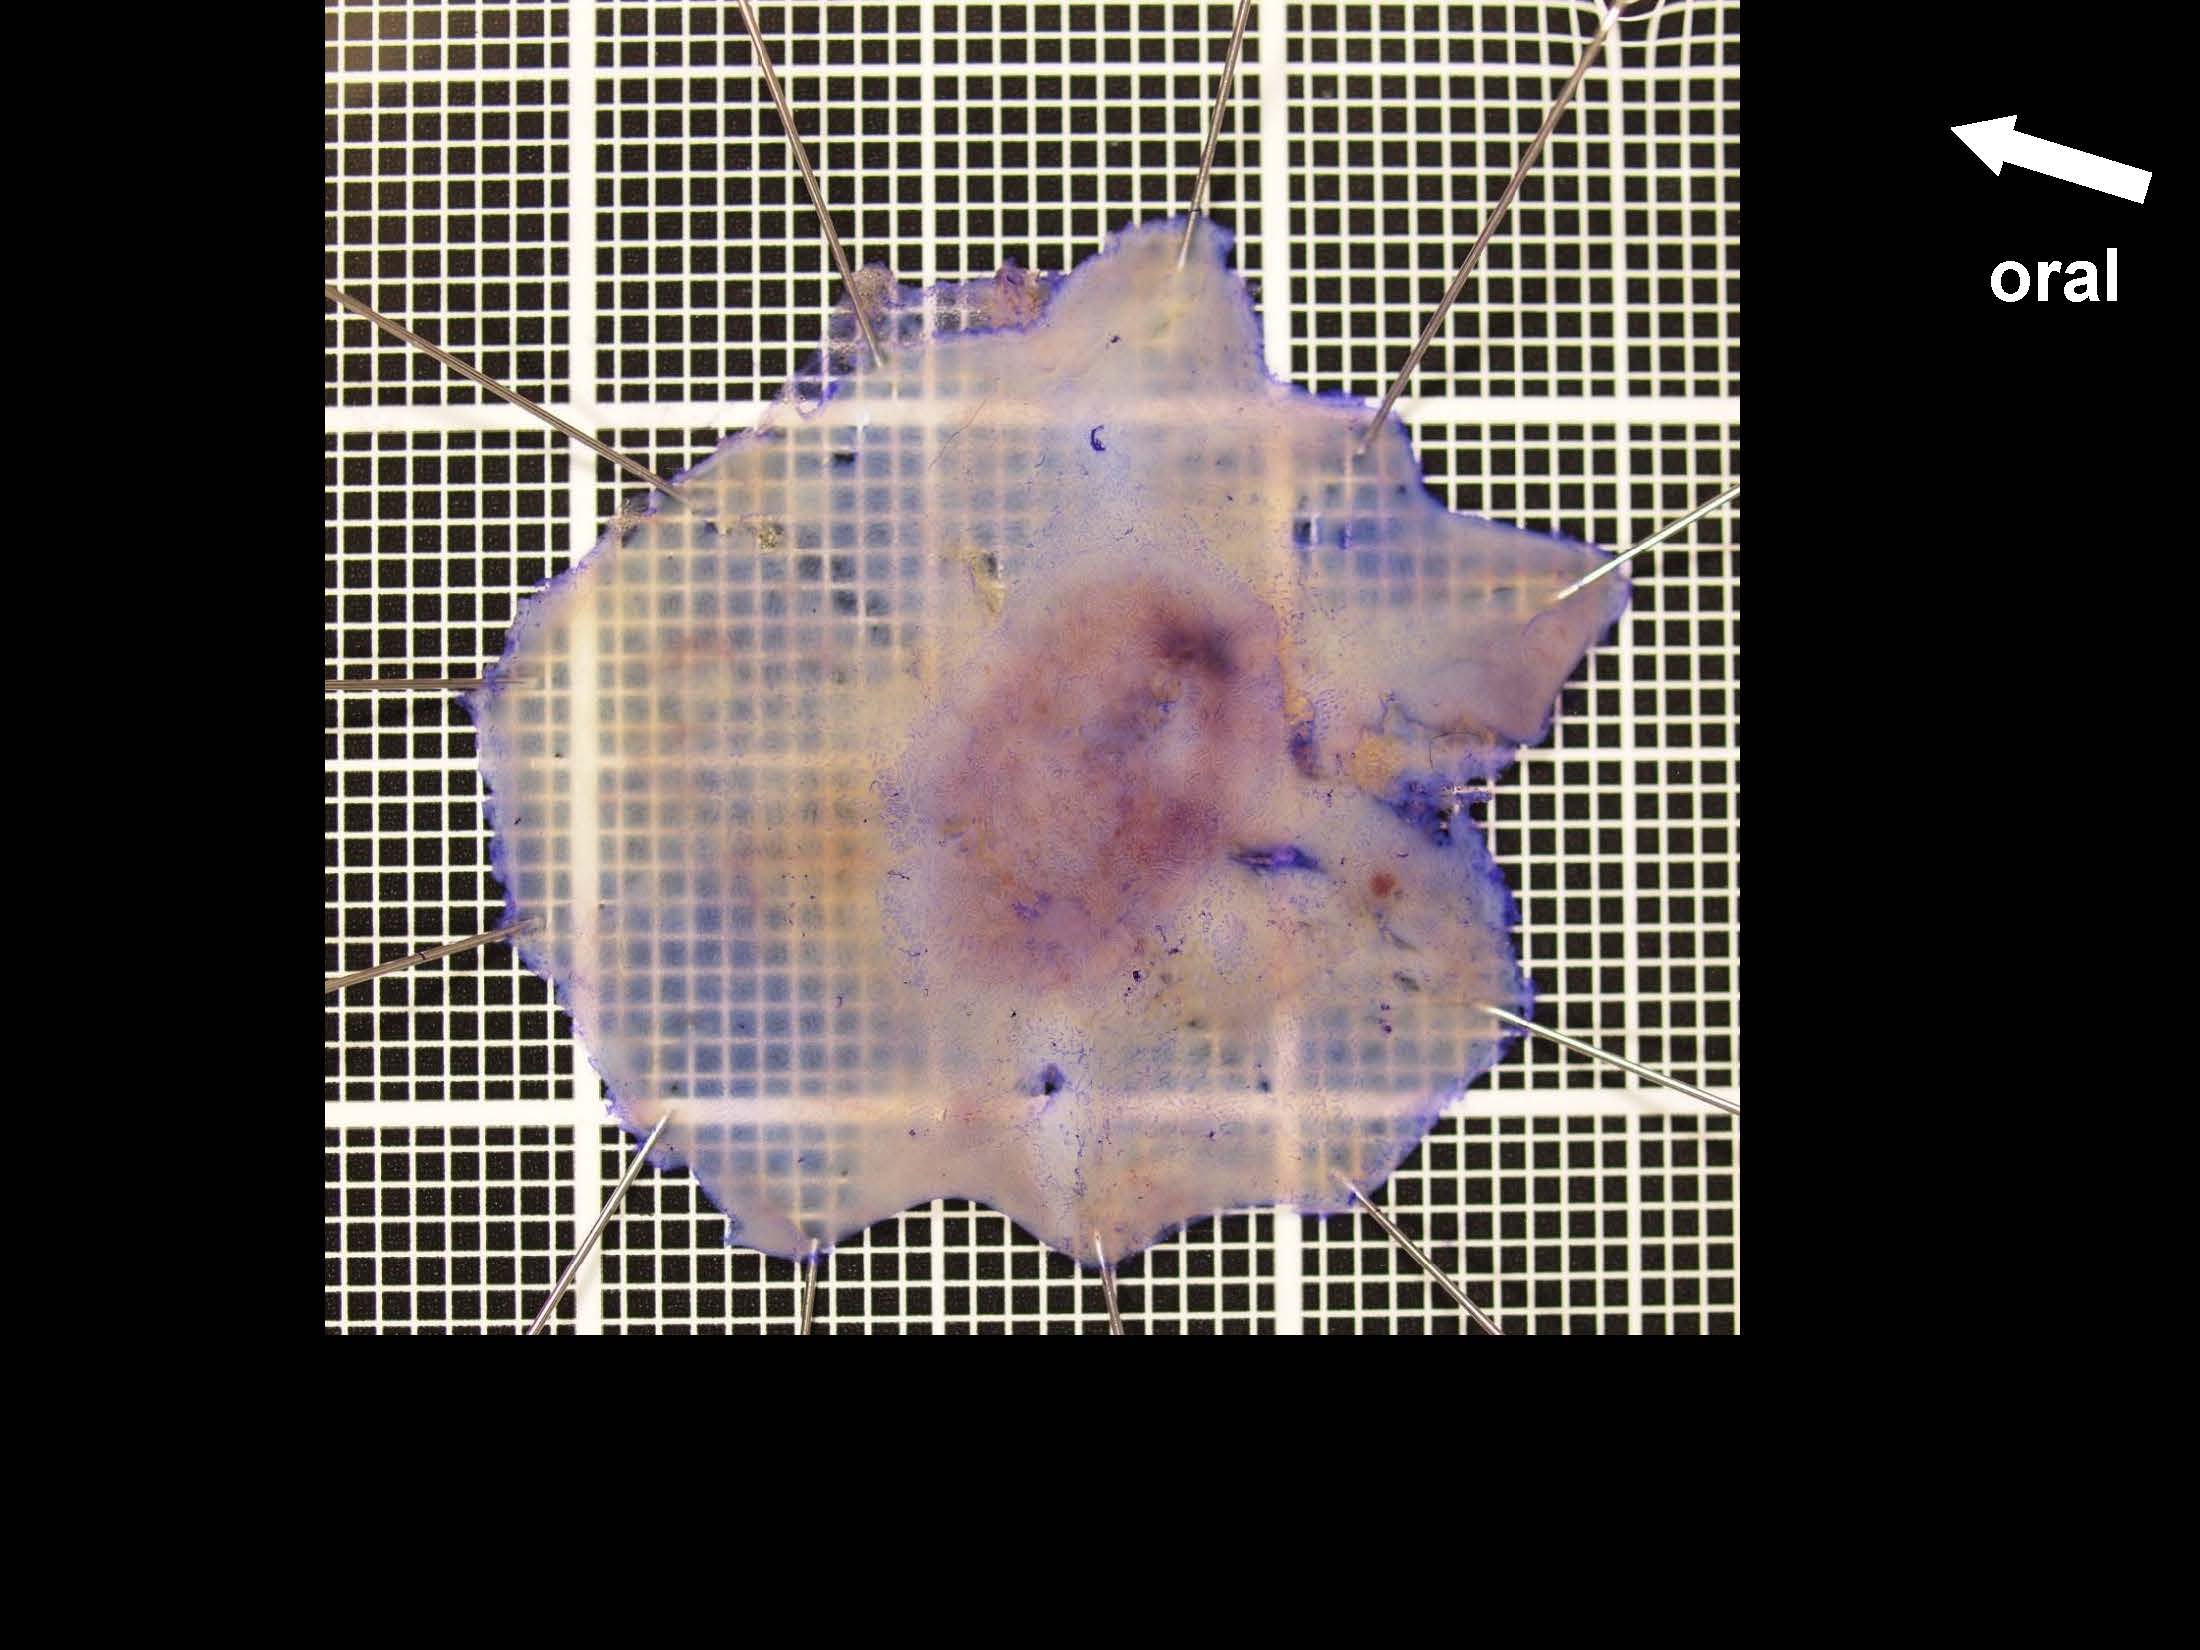

消化管Mapping~大腸~ 2021.10.27

消化管Mapping

消化管Mapping~大腸~

消化器内科

内視鏡検査・治療